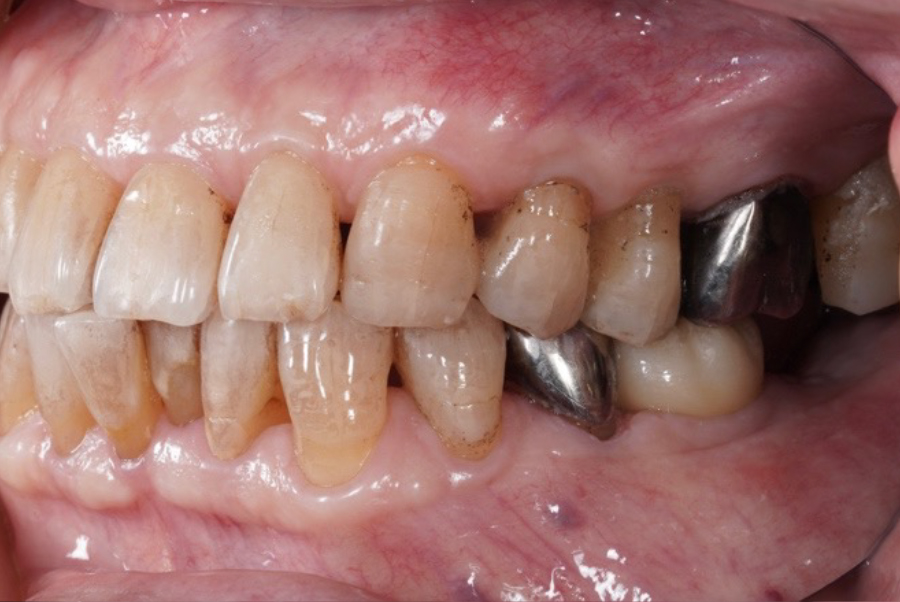

【治療後の状態(After)】

インプラント埋入後は良好に治癒し、最終補綴装着後はしっかりとした咀嚼機能が回復。

「違和感なく噛めるようになった」とご満足いただいています。